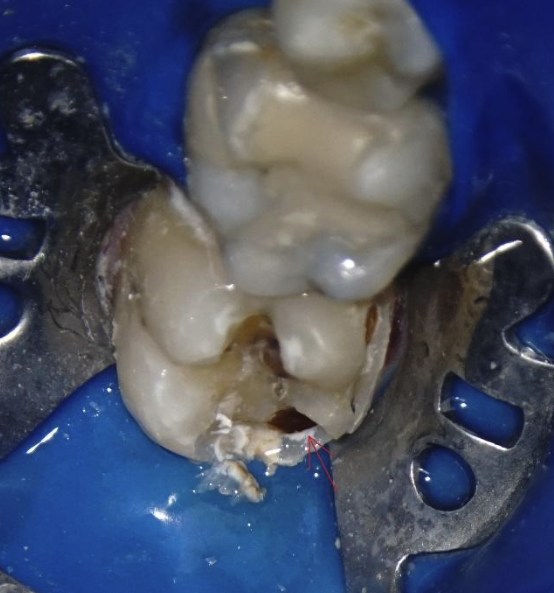

În Fig. 2 se poate observa câtă substanță dentară rămâne după îndepartarea țesuturilor afectate de carie; în cazul acesta pierderea crestelor marginale cât și a pereților vestibulari și orali indică necesitatea utilizării unei coroane parțiale.

Figura 2. Dintele 3.6 după îndepărtarea cariei si a obturației anterioare